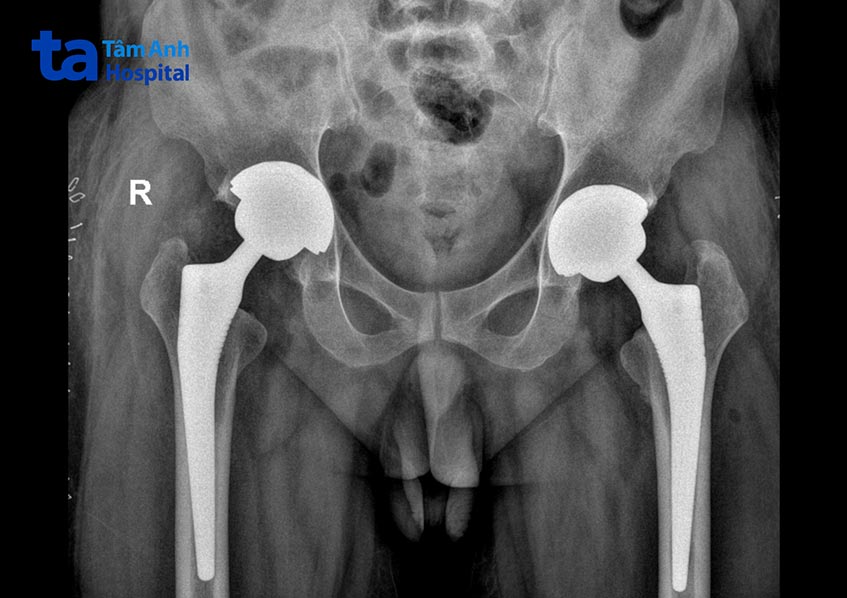

Anh Trương Công Bền (36 tuổi, Trà Vinh) đến thăm khám tại Bệnh viện Đa khoa Tâm Anh TP HCM trong tình trạng đau nhức khớp háng, đi lại khó khăn trong thời gian dài. Thông qua kết quả chẩn đoán hình ảnh, ThS.BS.CKI Mai Hoàng Dương cho biết người bệnh bị hoại tử chỏm xương đùi 2 bên.

Anh Bền được chỉ định thay khớp háng toàn phần ở cả 2 chân bằng đường mổ lối trước, không cần bắt vít, đóng ổ cối kiểu Pressfit (ổ cối, chuôi xương đùi và xương vỏ chịu trọng lượng của khớp nhân tạo được gắn chặt vào nhau và không có chuyển động vi mô).